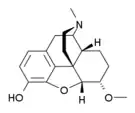

- Heterocodeine

Heterocodeine Heterocodeine |